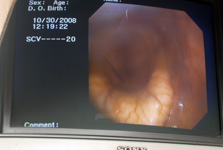

Chino Valley is able to investigate horses with poor performance. Typically, this may include examination of the larynx via treadmill endoscopy. Horses may then require a tie back proceedure which we perform at our hospital, or may need some form of LASER surgery.

This type of dynamic evaluation is very useful in determining if the horse has an upper airway abnormality affecting performance.

The examination is tailored to the type of work and the level of fitness for each horse, mimicking the speed and distance that the horse typically works.

On endoscopic examination, your vet will probably observe that the two cartilages in the larynx move differently as they cover the top of the trachea (this happens during swallowing to prevent food falling down the trachea).

If the arytenoid cartilages fail to move apart - because the recurrent laryngeal nerve is paralysed - or even if they move across only partially, the airway is compromised and the horse cannot inhale enough oxygen.

However, many other conditions including epiglottic entrapment, dorsal displacement of the soft palate, axial deviation of the aryepiglottic folds and many other upper respiratory conditions can be diagnosed with endoscopy.